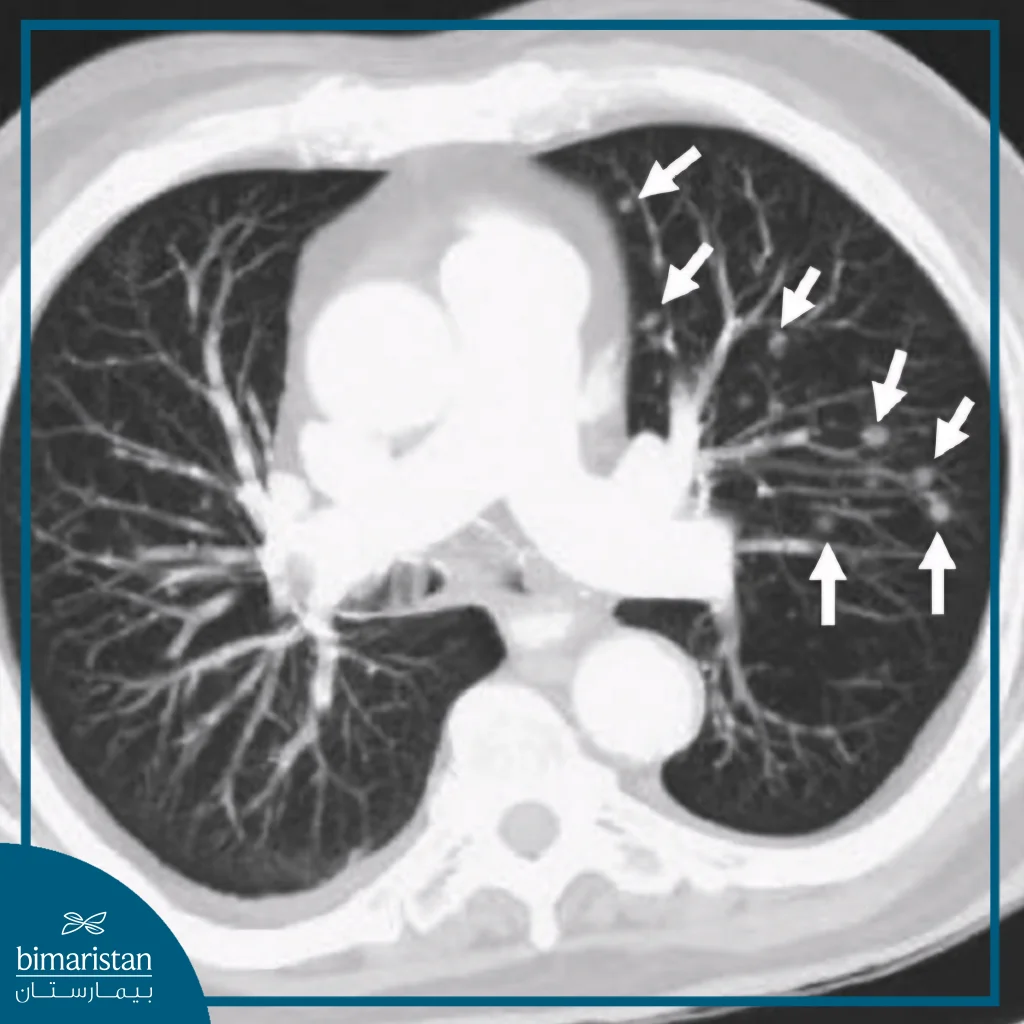

تُعرَّف العقيدات الرئوية بأنها مناطق صغيرة مستديرة أو بيضوية الشكل تظهر داخل نسيج الرئة، وتُشاهد عادة في صور الصدر الشعاعية أو في التصوير المقطعي المحوسب على شكل بقع بيضاء مميزة تختلف عن النسيج الرئوي الطبيعي المحيط بها، ويُطلق عليها أحياناً اسم “عقيدات الرئة” أو “النقاط الرئوية”، ويُعدّ أي تكوّن لا يتجاوز قطره ثلاثة سنتيمترات ضمن نطاق العقيدات، في حين يُصنَف ما هو أكبر من ذلك ككتلة رئوية.

غالباً ما تُكتشف العقيدات الرئوية بالصدفة أثناء إجراء تصوير للصدر بهدف آخر، كالفحص الشعاعي الروتيني أو التصوير المقطعي منخفض الجرعة المستخدم في برامج الكشف المبكر عن سرطان الرئة، وبعد اكتشافها يبدأ الطبيب بتقييم خصائصها من حيث الحجم والشكل وحدود العقيدة وكثافتها لتحديد مدى الحاجة إلى فحوص إضافية.

يُعتبر التصوير المقطعي المحوسب الوسيلة الأدق في تشخيص هذه العقيدات، إذ يُظهر تفاصيل دقيقة للبنية الداخلية ويسمح بمقارنة حجمها مع صور سابقة لتحديد ما إذا كانت مستقرة أو متزايدة. غالباً ما تُعدّ العقيدات الصغيرة ذات الحواف الملساء أقل خطورة، لذلك يُكتفى بمراقبتها دورياً عبر التصوير دون تدخل فوري. أما العقيدات التي تُظهر صفات غير طبيعية أو تغيّراً في حجمها بمرور الوقت، فتحتاج إلى استقصاءات إضافية تشمل فحوص الدم والبلغم للتحري عن الالتهابات أو العدوى المزمنة، أو إجراء تصوير متقدم لتقييم نشاط الخلايا داخلها وتقدير احتمال الخباثة.

أما العقيدات المتعددة، فهي تشير إلى وجود أكثر من بؤرة في الرئتين، وغالباً ما تُعبّر عن عملية مرضية أوسع نطاقاً مثل التهابات منتشرة، أو أمراض مناعية كالساركويد، أو في بعض الحالات عن انتشار سرطاني من ورم في عضو آخر، وتُقيَم هذه العقيدات من حيث توزيعها وحجمها وتشابهها فيما بينها، إذ يُعدّ التوزيع المتناظر والمتجانس أكثر ميلاً إلى الأسباب الالتهابية أو المناعية، في حين يُثير وجود عقيدات متفاوتة الشكل والحجم الشكّ بوجود نقائل سرطانية.